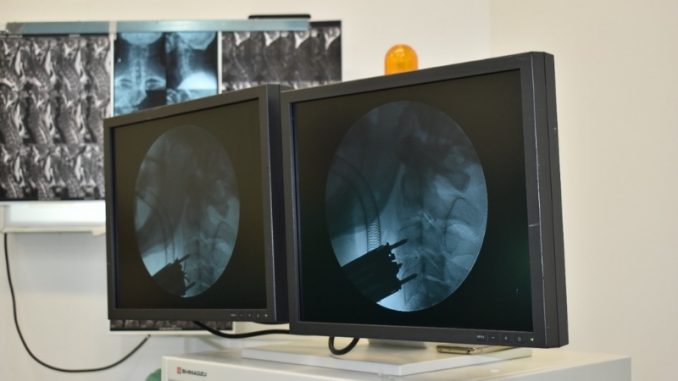

Através do Centro de Ortopedia Blumenau – COB, em maio, a equipe de Cirurgiões de Coluna, composta pelos Ortopedistas Dr. Fabio Kazuo Soejima, Dr. Fabiano Caumo e Dr. Felipe Martins, acompanhados pelo Proctor convidado, o Dr. Rodrigo Fetter Lauffer, realizaram pela primeira vez em Blumenau no Hospital Santo Antônio, uma cirurgia de Artrodese Cervical via anterior com cage Roi-C Dupla Ancoragem. Essa tecnologia é inovadora e dispensa a necessidade de utilização de placas e parafusos.

O design do implante é de “perfil zero”: alinhamento do cage e seu sistema de estabilização com a parede anterior dos corpos vertebrais. As Âncoras curvas e auto-estáveis, graças a seus clips laterais de estabilização, permitem estabilizar o sistema de ancoragem assim como o cage no espaço intersomático, tornando o procedimento mais seguro ao paciente.